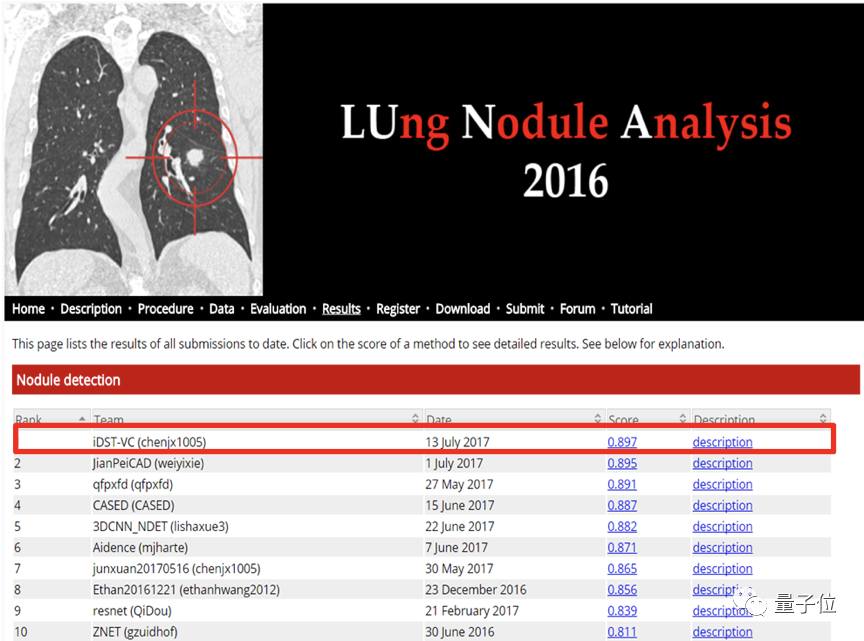

2017年7月,达摩院正式成立前夕,他们交出了一份“贺礼”——在国际权威的肺结节检测大赛LUNA16上打破世界纪录,凭借89.7%的平均召回率(在样本数据中成功发现结节占比的比例)夺冠。

华先胜说,这项工作“当时只道是寻常”,没想到直接为阿里达摩院新冠肺炎的CT自动诊断系统打下了基础。